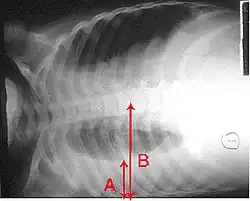

X-ray presentations of pneumonia may be classified as lobar pneumonia, bronchopneumonia, lobular pneumonia, and interstitial pneumonia.[75] Bacterial, community-acquired pneumonia classically show lung consolidation of one lung segmental lobe, which is known as lobar pneumonia.[42] However, findings may vary, and other patterns are common in other types of pneumonia.[42] Aspiration pneumonia may present with bilateral opacities primarily in the bases of the lungs and on the right side.[42] Radiographs of viral pneumonia may appear normal, appear hyper-inflated, have bilateral patchy areas, or present similar to bacterial pneumonia with lobar consolidation.[42] Radiologic findings may not be present in the early stages of the disease, especially in the presence of dehydration, or may be difficult to interpret in the obese or those with a history of lung disease.[24] Complications such as pleural effusion may also be found on chest radiographs. Laterolateral chest radiographs can increase the diagnostic accuracy of lung consolidation and pleural effusion.[41]